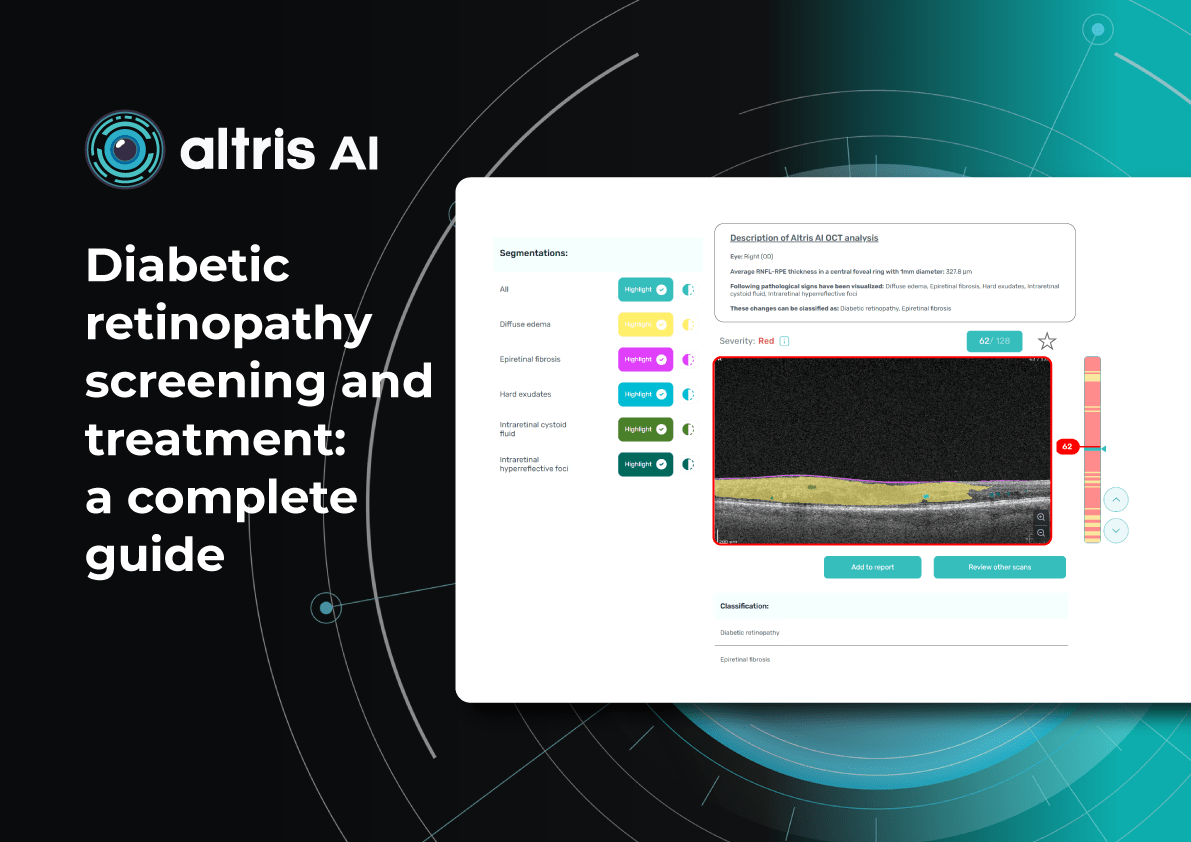

Dr. Maria Sampalis, OD, the owner of Sampalis Eye Care, Rhode Island, utilizes two such programs in her practice. To support her specialization in dry eye management, she employs CSI Dry Eye. Additionally, she uses Altris AI, an AI-powered platform for OCT scan analysis, to provide a second opinion and enhance diagnostic accuracy.

Dr. Sampalis finds that the Dry Eye software allows her and her staff to analyze symptoms and images comprehensively, improving patient care, time savings, and increasing diagnostic precision. See how OCT AI works here.

Her patients also appreciate Altris AI, which analyzes OCT scans for over 70 pathologies and biomarkers while also calculating the risk of developing glaucoma.

Eye Place, an optometry center in Columbia, also leverages Altris AI, among other cutting-edge technologies. They capture images using the Topcon Maestro2 OCT and use Image Net6 software to export DICOM files to the Altris AI platform.